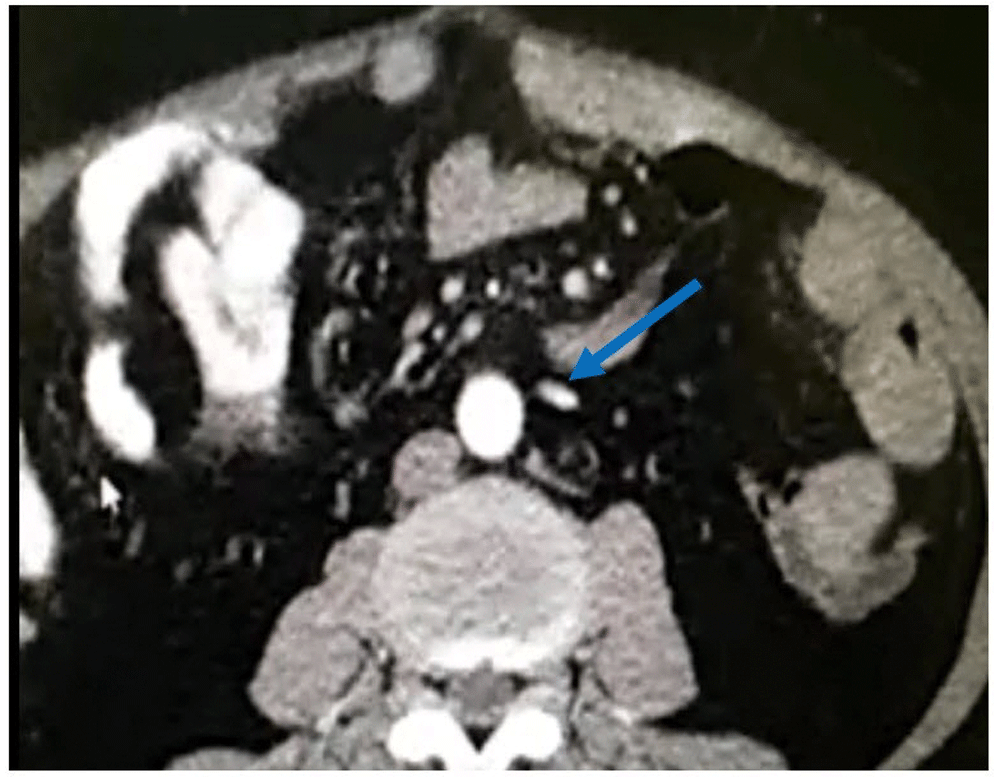

Abdominopelvic CT scan (Figure 2): A 130mm of segment of terminal ileum had diffuse wall thickening (3–8mm) associated with mesenteric fat. Narrow enhancement of inferior mesenteric artery with patchy filling defect, poor enhancement of terminal branches. Therefore, suspicions were: 1)vasculitis, 2)mesenteric ischemia.

Narrow enhancement of the inferior mesenteric artery can be observed (blue arrow).